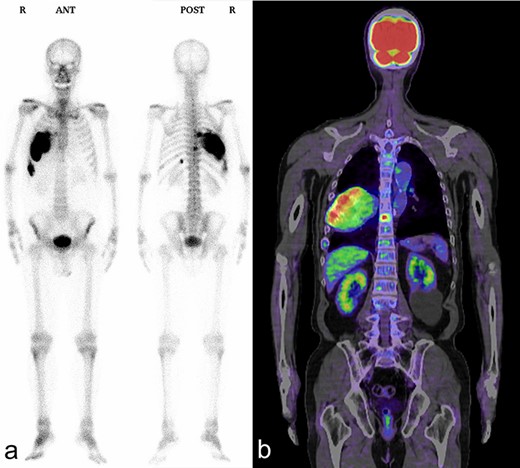

A 72-year-old man was referred to our department with a suspected tumor in the right rib. An abnormal shadow in the right chest was found during screening at 50 years of age. The patient was later followed up intermittently by a general physician (Fig. 1a and b). At 72 years of age, he was referred to our department because of a suspected malignant tumor. There were neither subjective symptoms nor abnormal physical findings. A blood test revealed an elevated level for alkaline phosphatase alone at 706 U/L. A pulmonary function test showed a percent vital capacity (%VC) of 78.8%, indicating a mild restrictive impairment. Plain radiography showed a radiopaque tumor measuring 12 × 9 × 18 cm that was connected to the seventh rib in the right thoracic cavity (Fig. 1c). When compared to previous images, the tumor had gradually grown over the preceding 22 years. Computed tomography (CT) showed an extra-osseous tumor-like lesion with calcification, cortical destruction of the right seventh rib and a similar small lesion in the right ninth rib (Fig. 2). Moreover, lesions were also detected in the ninth thoracic vertebral body. Magnetic resonance imaging (MRI) revealed a lower signal intensity inside the lesion compared to the muscle on T1-weighted images and a mixture of low and high intensity on T2-weighted images, while enhancement was observed in the lower intensity area on T2-weighted images (Fig. 3a and b). Bone scintigraphy and positron emission tomography/computed tomography (PET/CT) revealed an increased uptake in the right seventh and ninth ribs and ninth vertebral body, and the right seventh rib showed a high standard uptake value at 7.67 on PET/CT (Fig. 4a and b).

Bone scintigraphy and PET/CT shows an increased uptake in the right seventh and ninth ribs and ninth thoracic vertebral body. (a) Bone scintigraphy; (b) PET/CT.